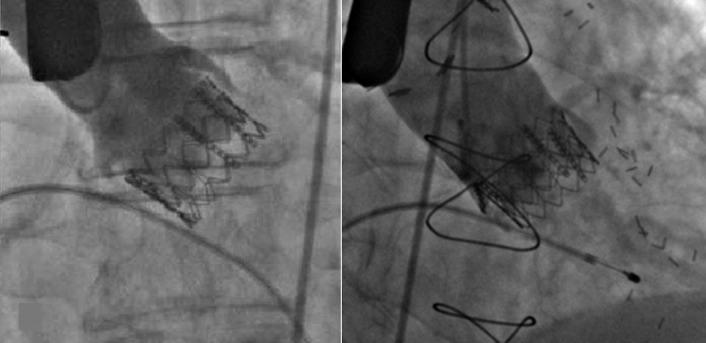

Transcatheter/percutaneously inserted heart valves are increasingly implanted. Most commonly, they are inserted into the pulmonic position or right heart conduits in the previously repaired congenital heart disease population ( Figs. 13-1 and 13-2 ) and into the aortic position ( Table 13-1 ; Graphics 13-1 and 13-2 ; Figs. 13-3 to 13-10 ), but they can also be placed into atrioventricular valve positions and into bioprostheses or conduits in any position.

Percutaneous valves are generally supported by radiographically obvious stents, the design of which allows for initial contraction of the prosthesis onto a catheter and release/self-expansion from the catheter.

Percutaneous/transcatheter heart valves are constructed of either bovine jugular venous valves that are suspended on wire mesh cages (Bonhoeffer design/Melody Transcatheter Pulmonary Valve–TPV, Medtronic), or consist of a valve created from bovine pericardial tissue that is suspended on wire mesh cages (Edwards Sapien and Medtronic CoreValve). Percutaneous aortic valve implantation is currently one of the most rapidly proliferating percutaneous interventions in the world ( Figs. 13-11 to 13-13 ).